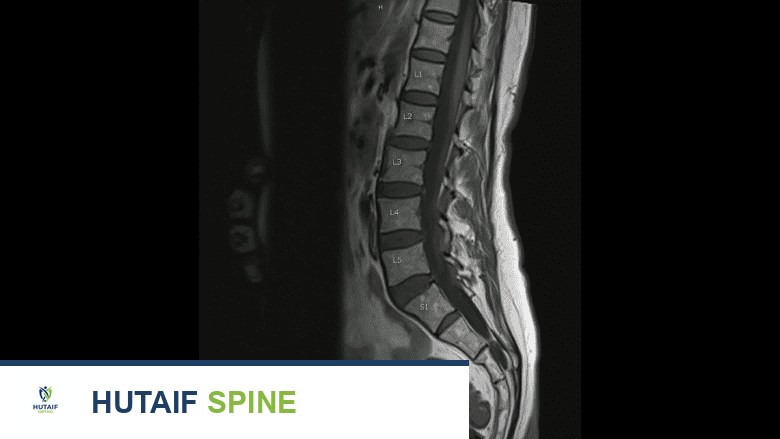

الفحوصات الإشعاعية والتصويرية

بناءً على مستوى القلق والنتائج الأولية، قد يُوصي الأستاذ الدكتور محمد هطيف بإجراء واحد أو أكثر من الفحوصات الإشعاعية والتصويرية الموضحة أدناه لتأكيد التشخيص أو استبعاد حالات معينة.

التصوير بالرنين المغناطيسي

يُعد الرنين المغناطيسي مفيدًا للكشف عن الأورام والالتهابات والفتق الغضروفي لدى الأطفال والمراهقين.

يُعد التصوير بالرنين المغناطيسي نوعًا أكثر تقدمًا من الفحص مقارنة بالأشعة المقطعية، حيث يُوفر تفاصيل متعمقة للعظام، المفاصل، العضلات، الغضاريف، والطبقات الداخلية للأنسجة الرخوة المحيطة بالعمود الفقري والحبل الشوكي. يُعد الرنين المغناطيسي مفيدًا بشكل خاص للكشف عن الأورام، الالتهابات، والفتق الغضروفي لدى الأطفال والمراهقين. غالبًا ما يُعطى التخدير العام للأطفال الصغار الذين يحتاجون إلى تصوير بالرنين المغناطيسي لضمان بقائهم ثابتين أثناء الفحص.